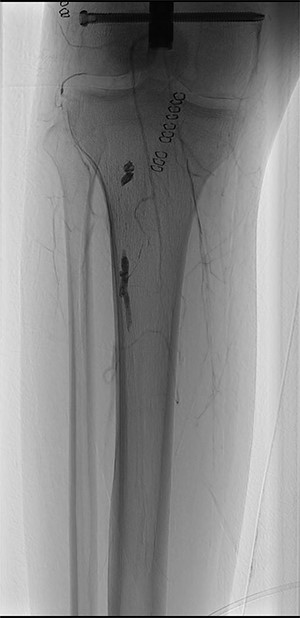

Completion angiography demonstrated the patency of the femoro-popliteal axis and of the tibial vessels (Fig. 3). Anterior and posterior fasciotomy of the leg was performed. At the end of the procedure a CW-Doppler was made showing triphasic-flow in the anterior and posterior tibial artery.

Completion angiography demonstrating patency of the popliteal artery, anterior tibial artery, posterior tibial artery and peroneal artery.